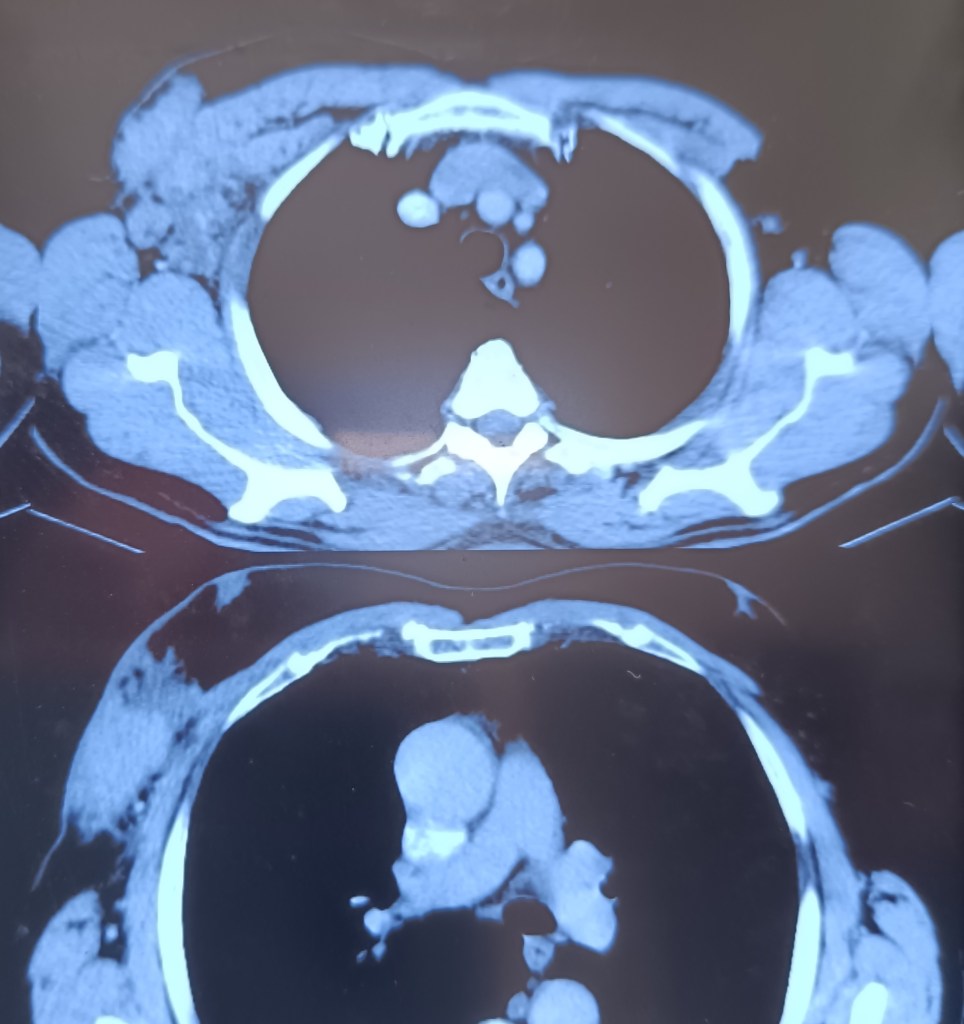

A 50 years old man presented with a slowly growing mass in the right side of upper chest and towards the axilla for the last 5 months. On examination it was irregular and hard to palpation; USG showed it to be 118x57x19 mm in dimensions along with a few lymph nodes in axilla, largest being 42×18 mm. FNAC showed cutaneous lymphoid hyperplasia with axillary lymph nodes being reactive. The whole mass was excised along along with some enlarged lymph nodes. Biopsy revealed a rare type of diagnosis – follicular lymphoma which was found to be very rare to occur isolated in the chest wall.